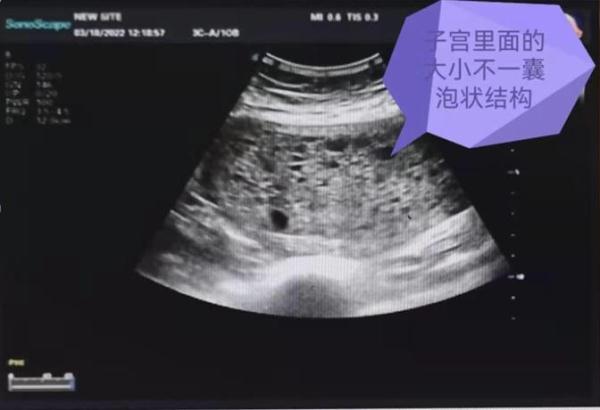

(上图:超声检查发现的异常特征)

来自湖南石门的李女士,最近半年来总感觉月经较以往多了许多,以前三天左右就会干净的“大姨妈”要淅淅沥沥的拖一周甚至半个月左右,关键的是慢慢地下腹部还鼓起了一个坨。李女士赶紧在家人的陪同下,来到湖南省第二人民医院(湖南省脑科医院)。通过检查,医院肿瘤科何伟凤教授发现李女士的子宫腔里长了一串串形似葡萄的肿瘤,并且子宫比同龄的女性要大,血清中提示可能妊娠的β-人绒毛膜促性腺激素(β-HCG)达到了300000mU/ml以上!通过进一步病理检查发现,原来李女士是患上了一种原发于胎盘滋养细胞的恶性肿瘤——子宫的“侵蚀性葡萄胎”!

(上图示:磁共振检查发现子宫内面的多发囊泡状异常结构及宫旁的肿物)